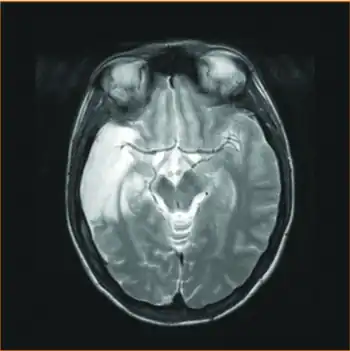

| MRI sequence - injury was sustained before PFO closure, most probably due to paradoxical embolism after documented deep venous thrombosis | |